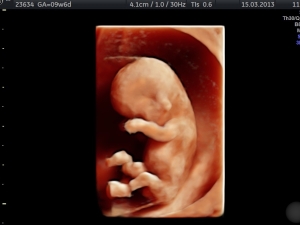

Sie können sich rund um die Uhr selbst den gewünschten Termin buchen. Besuchen Sie ggf. vorab den „Schwangerschaftskalender“ und dann die unsere Terminvergabe auf